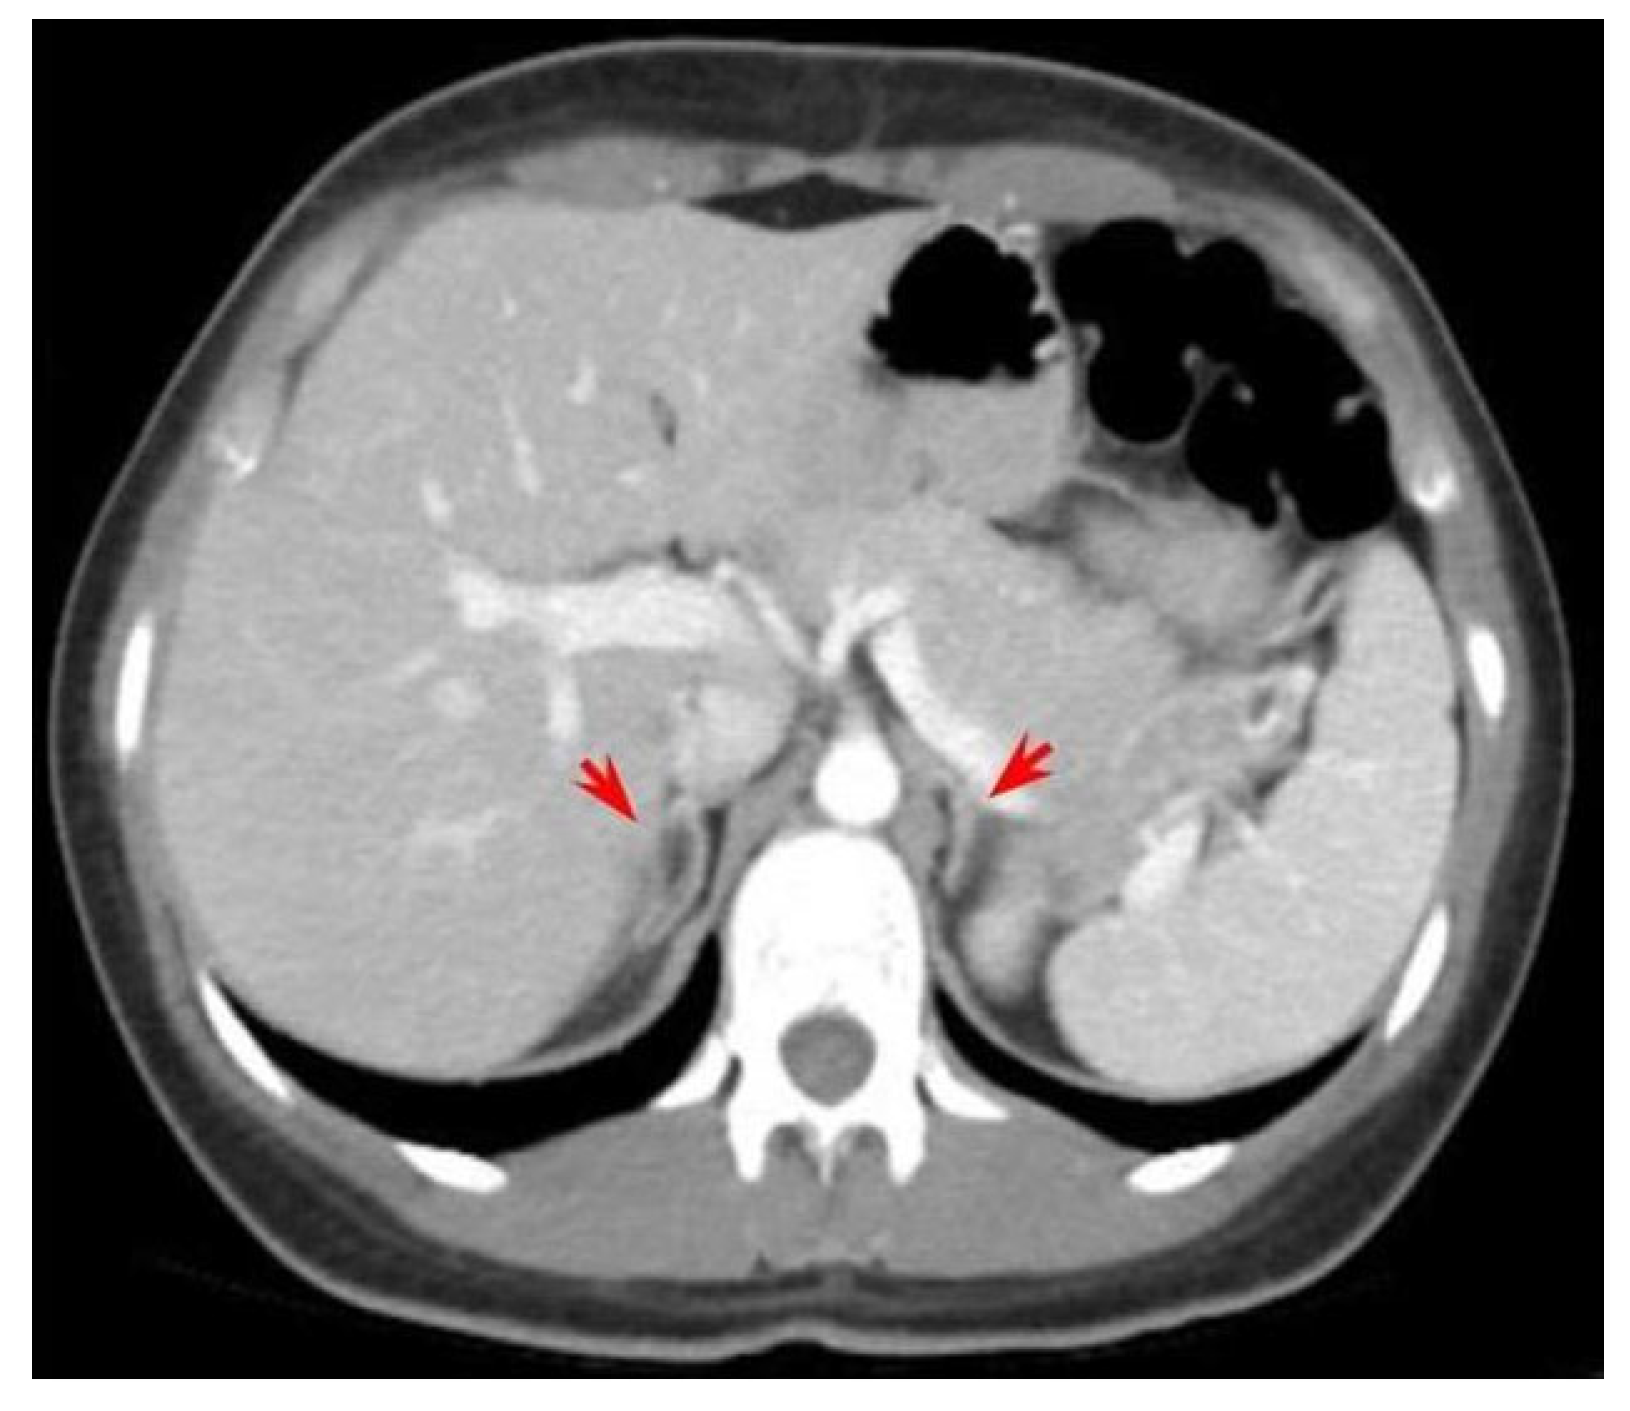

| [54] | BAT: 10.6 × 7.0 × 5.5 cm (L) + 8.1 × 4.2 x3.3 cm (R) | ML | Palpable mass → bilateral adrenalectomy |

| [60] | giant BAT (R > L) | ML | Abdominal pain → bilateral adrenalectomy → 1.56 kg (L) and 3.05 kg (R) |